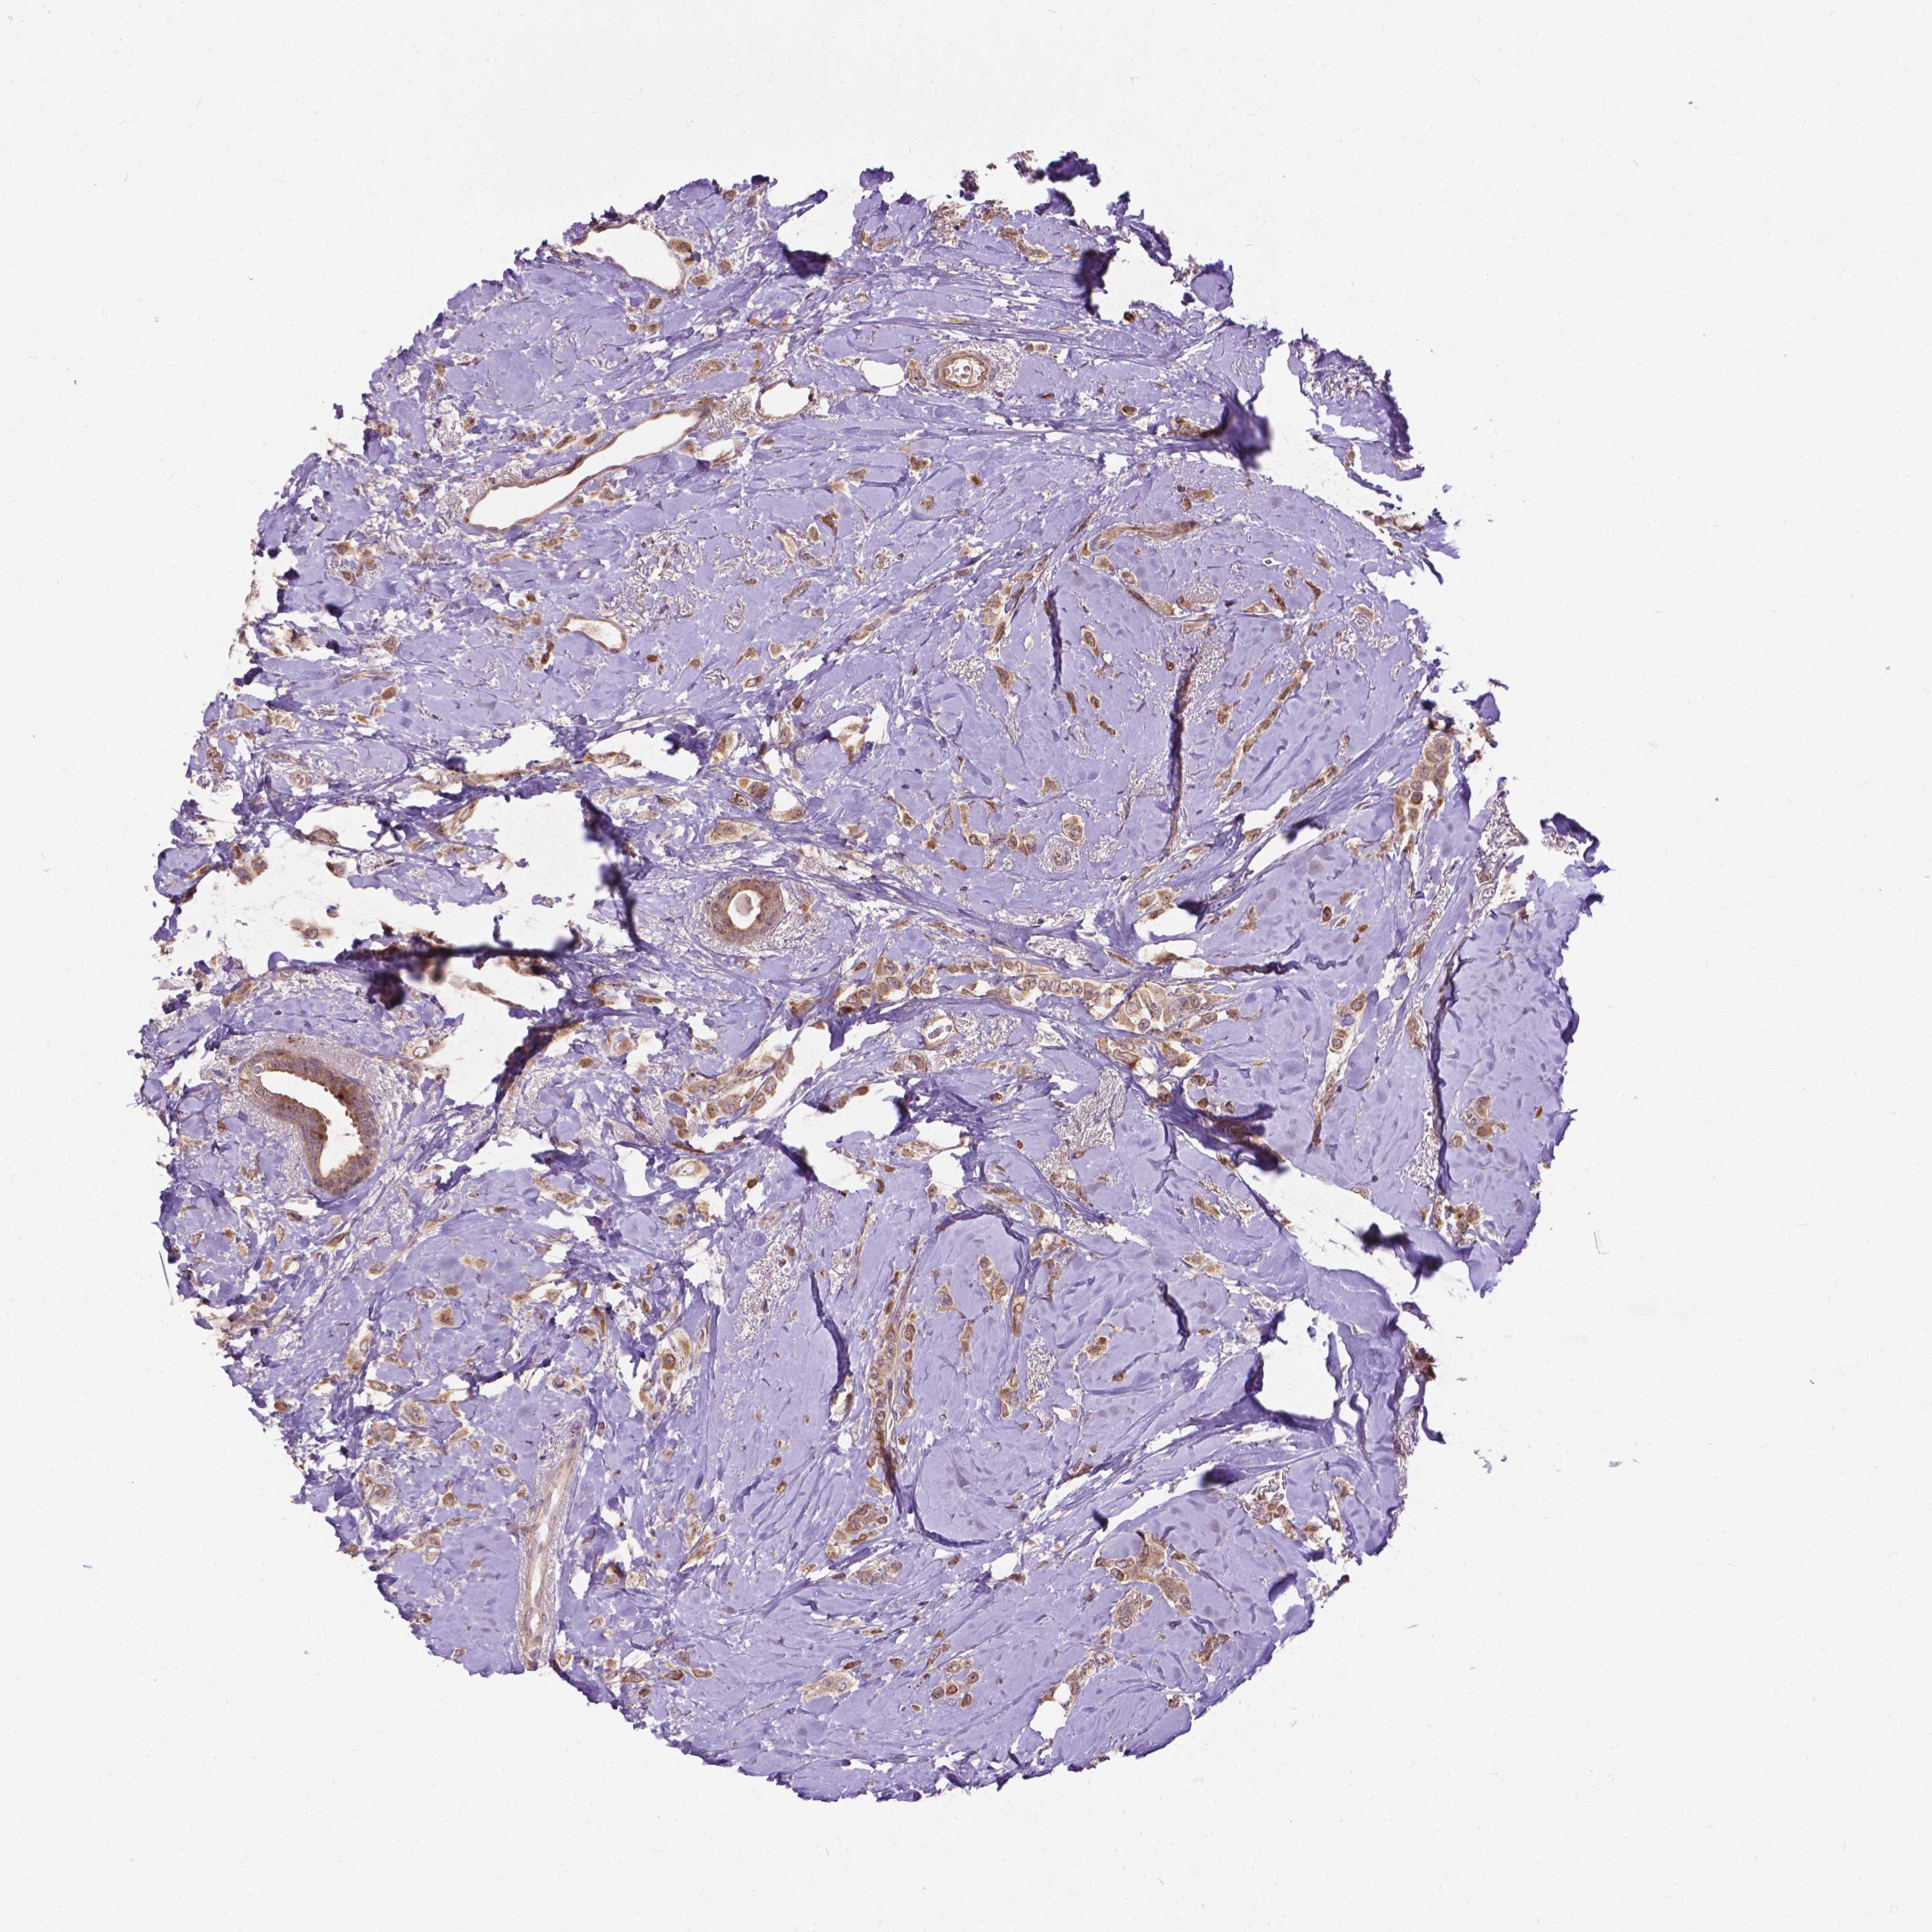

BRCA TCGA BRCA VALIDATION PROTEIN EXPRESSION

Breast cancer

Human cancer